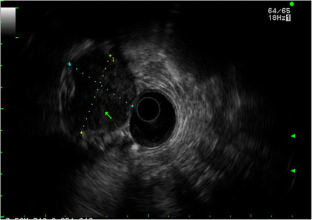

• Advances in endosonography (EUS) and immunohistochemical staining can distinguish these lesions from other intramural and GI tract tumors and are an essential part of the diagnostic and staging workup.

• The advent of EUS-guided fine needle biopsy (FNB) allows for large core tissue acquisition. This has replaced FNA and allowed for histologic analysis of large specimens, increased IHC confirmation, and personalized medicine.

• The cases presented in this report represent pathology-confirmed GISTs diagnosed at a large volume, community, tertiary referral GI oncology program during July 2012 through May 2016. Follow-ups for each patient have discovered no recurrences to date.